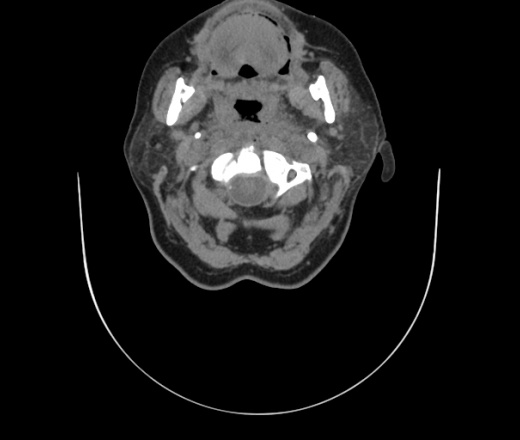

Женщина поступила в х/о спустя 4 дня после того как при употреблении карася подавилась костью.

Наличие газа в средостении на протяжении тел С2-С6 (медиастинальна эмфизема); рыбная кость на уровне тела С6.

При всем уважении, но говорить о медиастинальной эмфиземе, оценивая мягкие ткани шеи, как-то слишком резко. На мой взгляд, это ретрофарингеальное пространство.

Эвакуировали почти 100мл гноя. Но кость не смогли найти. Думаю что она даст дальнейшее ослоднение. Эндоскопически за черпалонадгортаной звязкой не смогли зайти в пищевод, все мягкие ткани отечные, просвет пищевода сдавлен. По всей видимости параэзофагеальная клетчака тоже задействована. Эмпиема, если ее можно так назвать, незнаю как правильно дошла до уровня яремной вырезки. Чем закончиться напишу. Ждем медиастинита.

Флегмона заглоточного пространства шеи, только операция, флегмоны вскрывают. Риск медиастинита.

Согласен с Вами; конечно, наличие газа в клетчатке ретрофарингеального пространства (затмение с опечаткой..). К сожалению, процесс "продвигается" к медиастиниту. Но почему никто, не отмечает наличие рыб. кости; или это для Всех очевидно?

Кость то мы сразу выявили, размеры где то 17*2мм, но ее так и не получается найти в этой каше